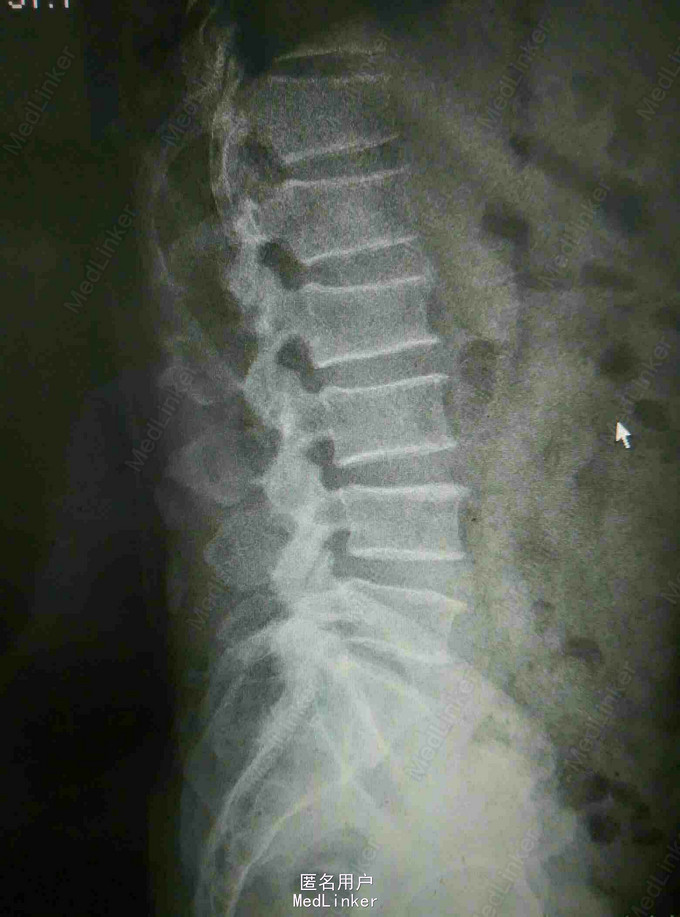

腰痛4年,双下肢麻痛无力伴二便障碍1月 患者老年男性,四年前无明显诱因出现腰痛,当时无双下肢麻痛及大小便障碍。四年来症状反复发作,未做特殊处理,近一月来患者腰痛症状加重,出现双下肢麻痛无力,伴有大小便障碍,为进一步治疗入我院。

查体:患者腰围固定,腰骶部及椎旁可有轻压痛,双侧臀部及大腿外侧放射痛,双下肢肌力减退,膝踝反射减弱 辅查:我院CT及外院核磁提示L4-5椎间盘向后膨出伴椎管重度狭窄,马尾神经受压

诊断:腰椎间盘突出 马尾神经受压 双下肢不全瘫 治疗:腰椎后路减压植骨融合内固定术